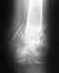

Заключение ренгенографии правой кисти руки: перелом основания 3 пястной кости со смещением обломков, в стадии консолидации. Перелом крючковатой кости со смещением в стадии консолидации. Тыльный вывих 3,4 пястной кисти. Травма 25 апр.2010г. операции не было. Для восстановления функции где сделать операцию? Проживаю г.Ревда Свердловской обл.